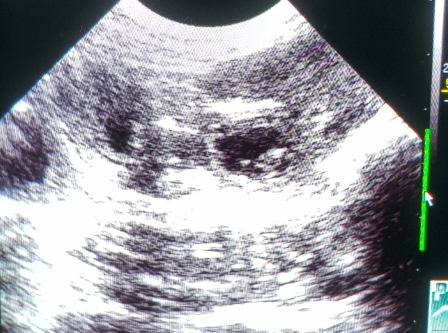

Wie schnell sie auch insgesamt wachsen, könnt ihr hier sehen:

Ich konnte mich nicht zurückhalten und musste heute noch einmal nachsehen :)

Franzi und ich haben viele Fruchtblasen, muntere Babys und schlagende Herzchen gesehen!

Zählen war unmöglich, wie ihr auf dem dritten Bild sehen könnt,

haben sich manchmal an einem Platz fünf Fruchtblasen geöffnet :O

Oft lagen zwei dicht nebeneinander, wie auf dem letzten..

Wir sind sehr gespannt!!!